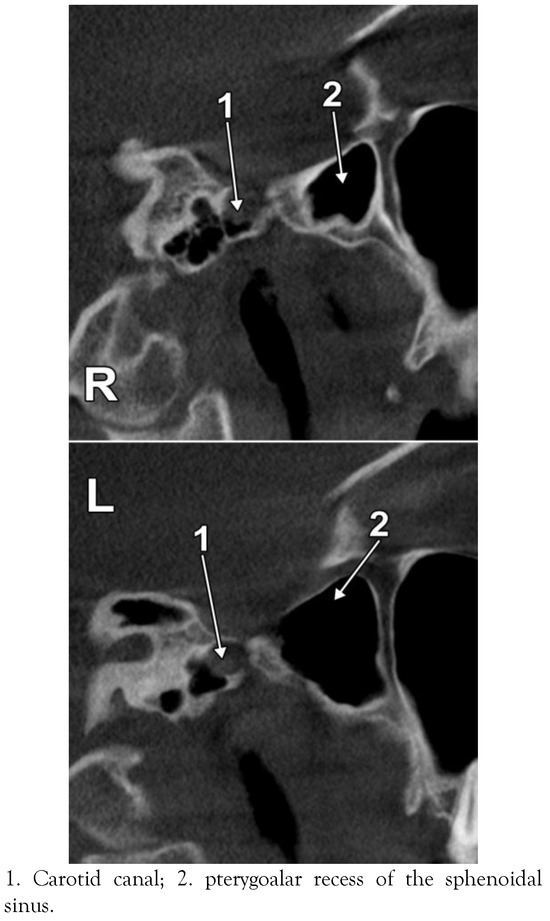

The Pneumatization Patterns of the Roof of the Parapharyngeal Space in CBCT

Introduction: The rhinopharynx and the parapharyngeal space (PPS) are complex anatomical territories located beneath the skull base. Thorough knowledge of the complex anatomy of the PPS is essential in treatment of pathologies such as parapharyngeal abscesses. The roof of the PPS is overlooked in anatomy. It was hypothesized that the pneumatization pattern of the PPS roof is individually variable, as determined by the variable pneumatization patterns of the sphenoid and temporal bones. The study was aimed at assessing the anatomy of the PPS roof in CBCT. Methods: The present study was performed retrospectively on a group of 35 subjects (37.1% males) evaluated by CBCT for various dental procedures. Results: The mean age of the group was 37.9 (SD: 14.2, range: 18 to 61). The major bony landmarks of the PPS roof were: the petrous apex with the carotid canal, the jugular foramen, the foramen lacerum, the sphenopetrosal fissure or suture, and the root of the pterygoid process. Variable patterns of pneumatization were determined by the petrous apex air cells and the pterygoalar recess of the sphenoidal sinus. As related to the individually pattern of pneumatization, the following types of the PPS roof were defined: (i) type 1 – not pneumatized PPS roof; (ii) type 2 – sphenoidal but not petrosal pneumatization of the PPS roof; (iii) type 3 – petrosal but not sphenoidal pneumatization of the PPS roof; (iv) type 4 – sphenoidal and petrosal pneumatizations of the PPS roof. Discussion: Although on the left side the degree of pneumatization was higher than on the right side, no statistical differences were recorded (p > 0.05). The pattern of pneumatizations in the PPS roof should be assessed when PPS involvement in otitis or sinusitis is considered. Full article